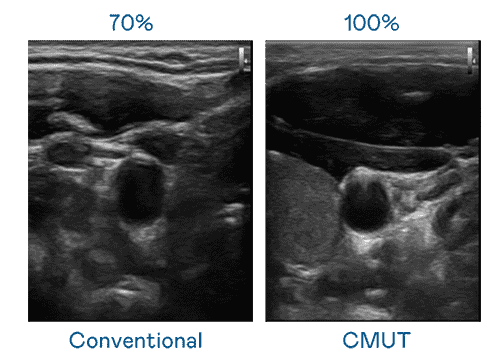

CMUT 技术是一种用电容式微机电元件来产生超音波讯号的技术。。。。与传统 PZT 压电式技术相比,,CMUT 频宽增加 30%,,,,更宽频的超音波讯号让影像解析度大幅提升,,,,是实现高影像品质医疗超音波扫描、、、促进精准医疗发展的关键技术。。

大频宽带来超清晰影像

超音波影像的解析度高低,,首先取决于探头能发出的讯号频宽。。。。z6尊龙 CMUT 可提供高清晰的超音波讯号,,,提供高频宽、、、、高灵敏度、、、、影像纹理细节更高的超音波影像,,,协助医护人员缩短影像判读时间及利用精准的医疗影像进行诊断。。